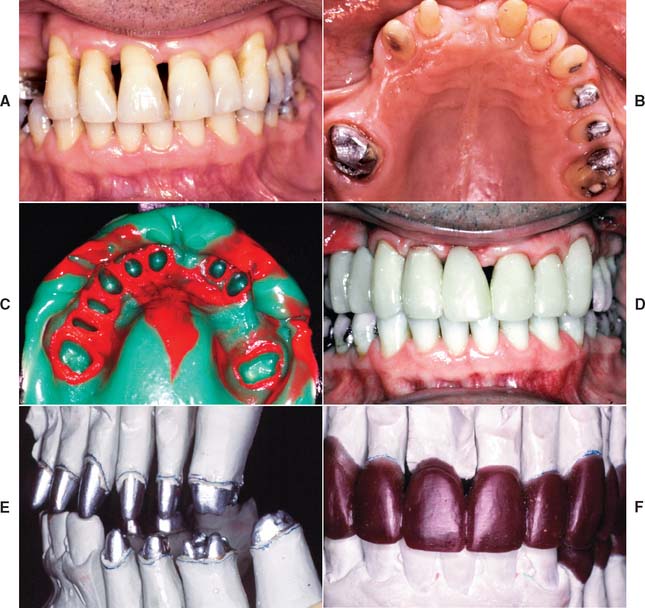

Fig. 32-12 Periodontal failure resulting from defective fixed prostheses. A, Inadequate margins and contour. B, Appearance before surgery. C, Flap reflected. D, Appearance after surgical recontouring. E, Radiograph of new cast restorations. F, Replacement restorations.

(Courtesy of Dr. C. L. Politis.)